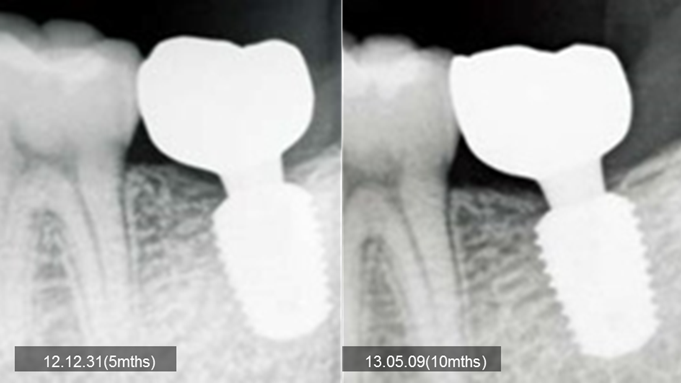

Clinical case: Bone growth in deepest thread of 8.0mm AnyRidge fixture

- Courtesy of Dr. Kwang Bum Park -

Clinical case: Bone filling into the bottom of deepest thread at 8.0mm AnyRidge fixture

Keywords

AnyRidge, Knifethread ,extraction socket, ,initial stability ,Allograft, ,osseointegratio ,Dr. Kwang Bum Park, , Mandibular, Single replacement, AnyRidge, Mega-oss,

Products used

Implant system-AnyRidge, Regeneration-Mega-Oss